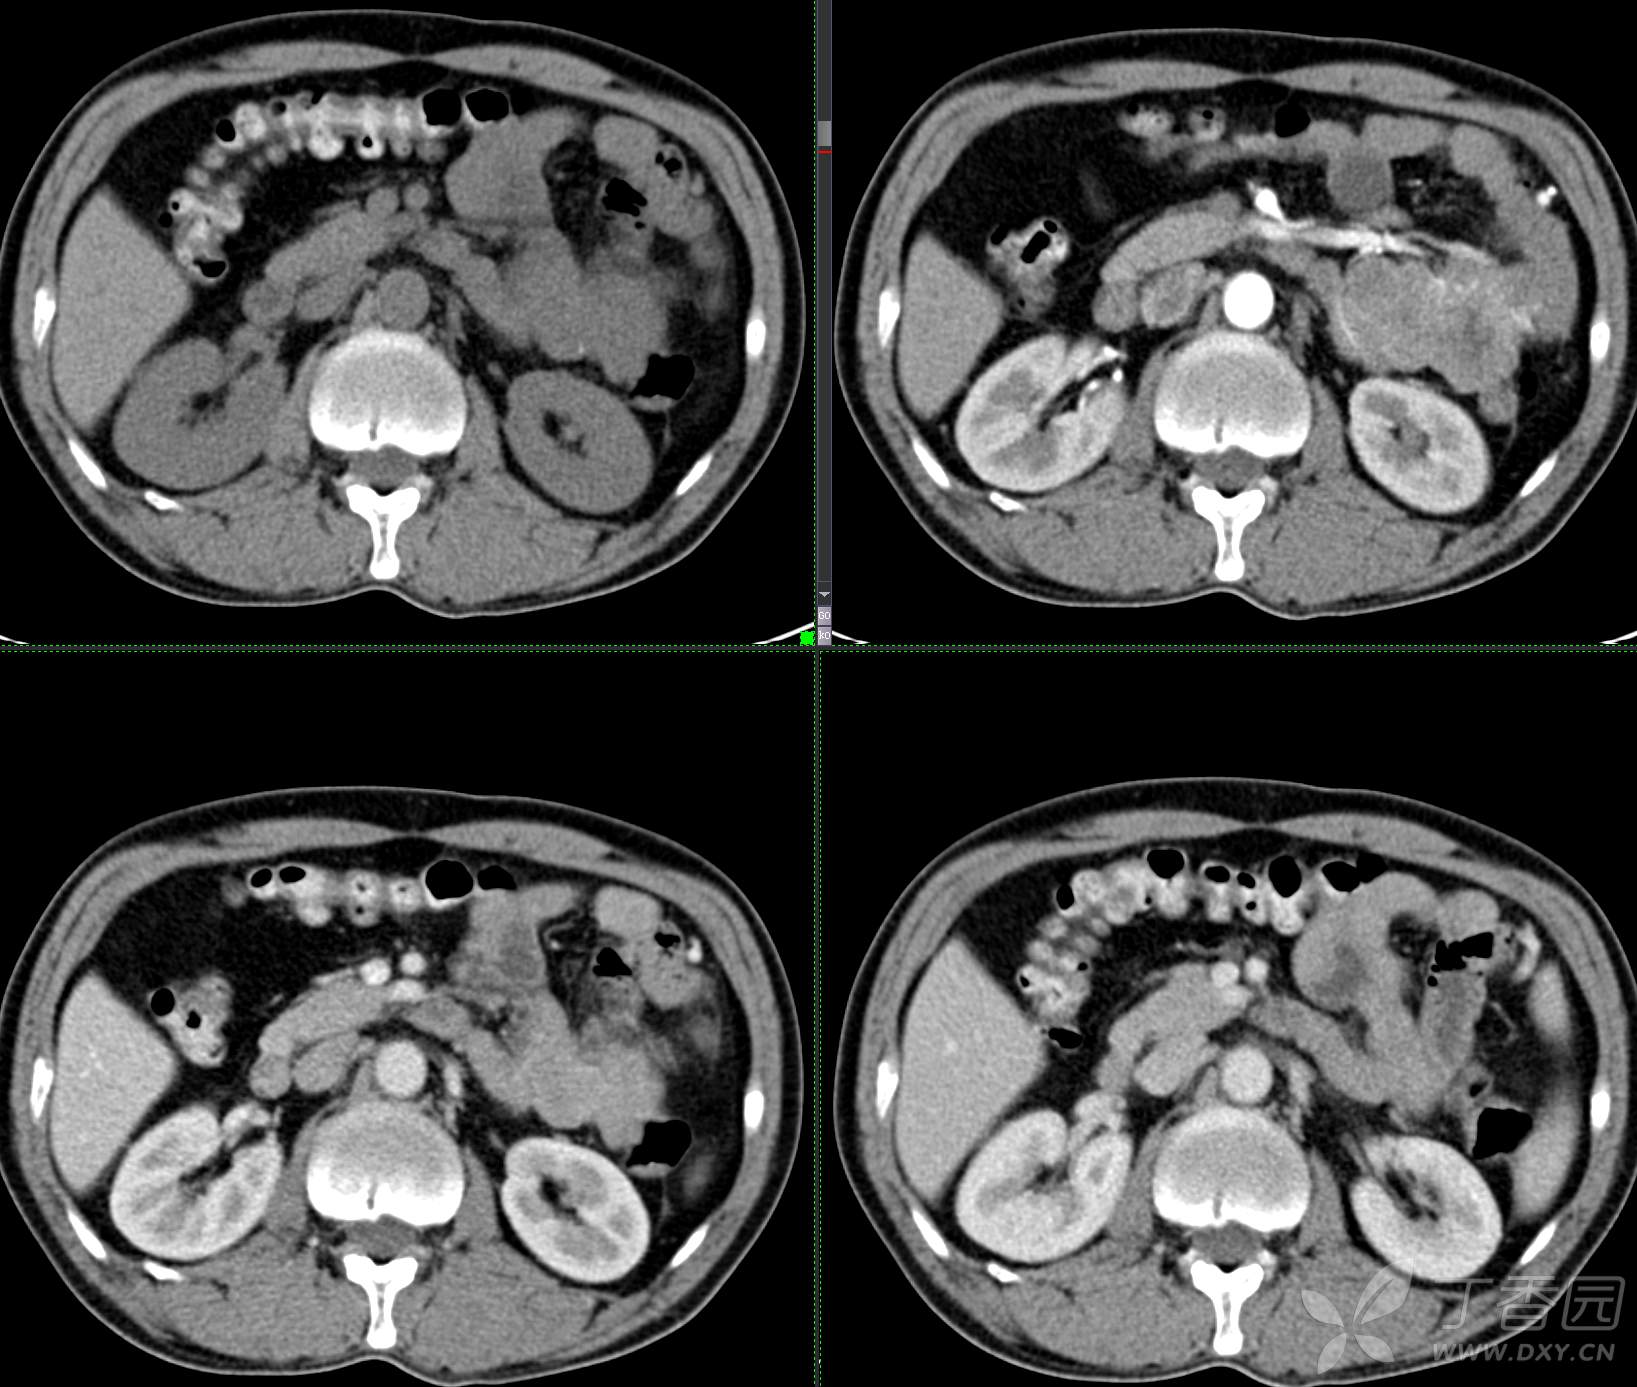

讨论:小肠病变,间质瘤?淋巴瘤?小肠腺癌?